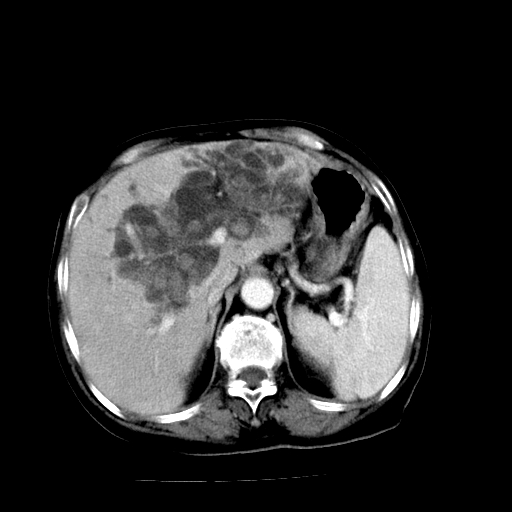

以下是引用卜一在2009-4-7 5:06:00的发言:[br]左右肝内胆管结石伴扩张合并胆系感染;不除外胆管细胞癌可能。支持! [br] [br]

以下是引用随光逐影在2009-4-7 8:21:00的发言:[br]肝内外胆管多发性结石并肝内外胆管扩张;胆系感染。